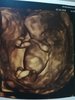

To i ja zamelduję tutaj o wczorajszym badaniu. Bąbelek ma 5,6 cm, wielkość zgadza się z OM, czyli 11+6. Strasznie się wiercił, ciężko było złapać cokolwiek

. Cudownie to wyglądało jak co chwila nawiewał przed sondą